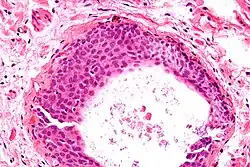

- Uniform nuclei with irregular borders and nuclear grooves (insert image).

High magnification micrograph of a Brenner tumor showing the characteristic coffee bean nuclei which are also seen in Walthard cell rests. H&E stain.